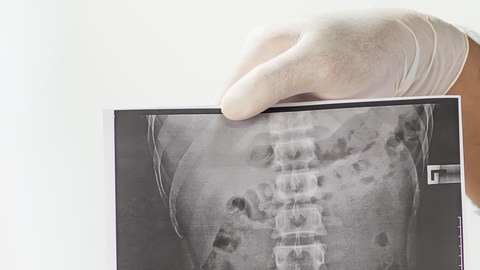

Crédito: shutterstock

La espondilitis anquilosante es una enfermedad inflamatoria que puede causar la fusión vertebral. Esta fusión reduce la flexibilidad de la columna y se forme una postura encorvada hacia adelante. Si las costillas están involucradas, la respiración honda puede ser complicada.